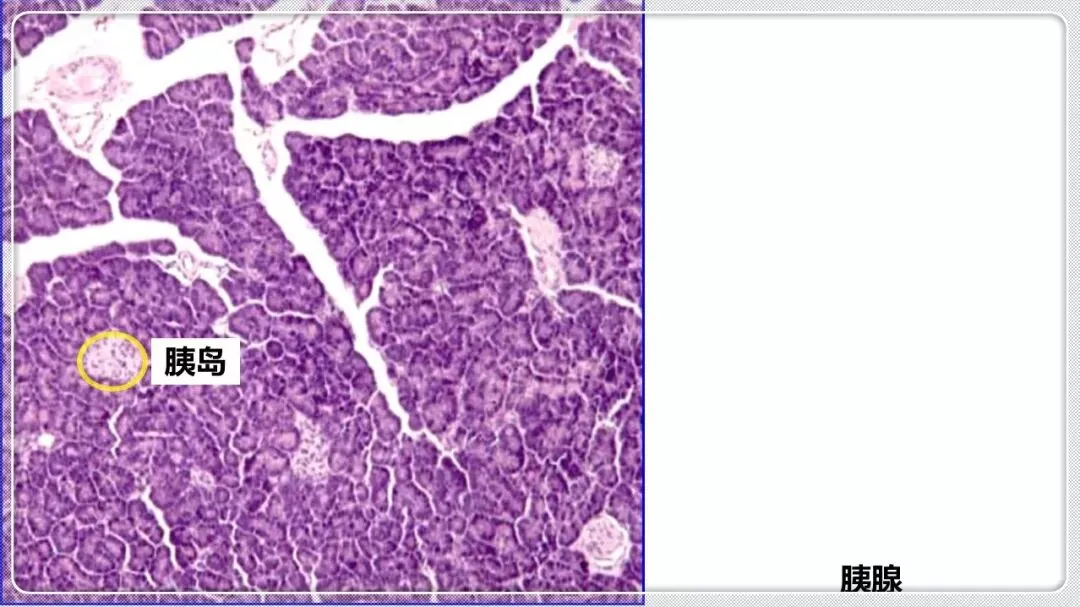

组织学与胚胎学笔记pdf【 常考图谱】

组织学与胚胎学 图谱